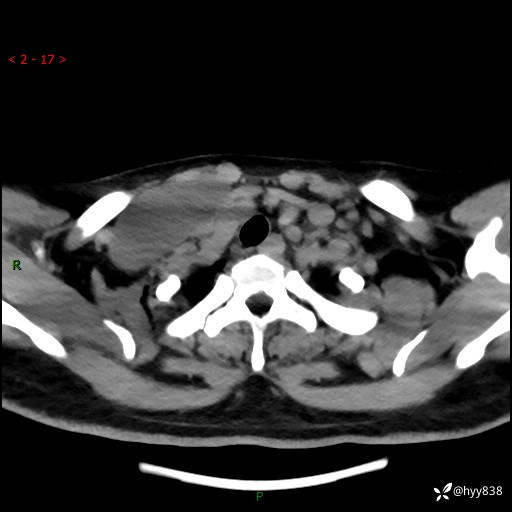

辅助检查:CT

颈部CT平扫

增强动脉期+静脉期